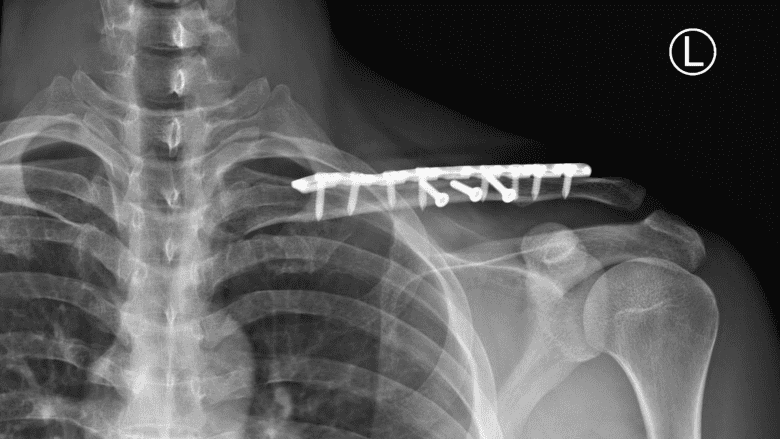

Fractured clavicle bone treated by open reduction internal fixation (ORIF) with plate and screws.

A common surgical procedure for clavicle fracture is open reduction and internal fixation (ORIF). This surgery involves exposing the fracture, realigning the bone fragments, and stabilizing them with plates, screws, pins, or rods.